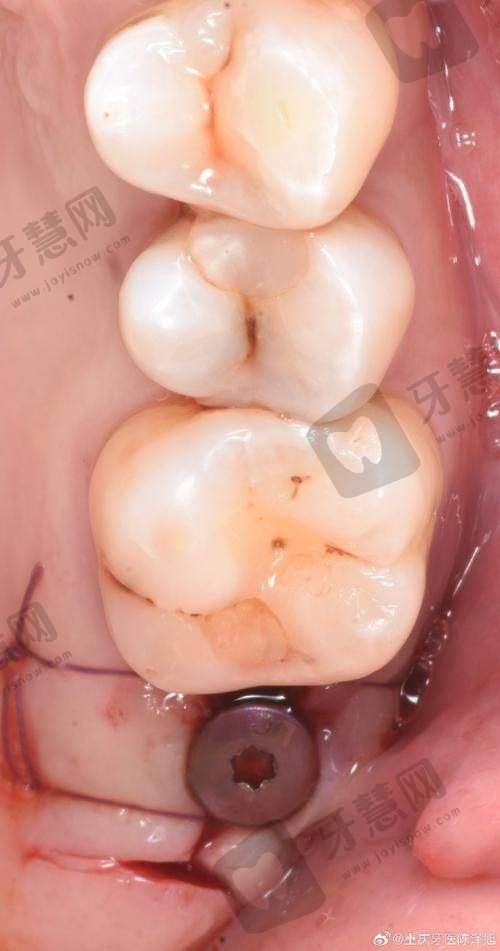

1. 口腔种植科:特色项目包括机器人辅助种植、即刻负重种植、骨增量技术等,尤其擅长处理牙槽骨萎缩、上颌窦提升等高难度病例。科室配备德国KAVO种植机器人和3D导航系统,通过术前CT扫描和计算机规划,实现种植体精细植入,对于骨量不足患者,采用自体骨移植或牵张成骨技术,90%患者可避免植骨手术。

首都医 科 大学附属北京口腔医院的核心竞争力在于其领跑的特色技术和人性化服务体系,尤其在口腔种植、正颌正畸、儿童口腔等领域形成独特优势。机器人辅助种植技术是医院的“王牌技术”,该系统由德国KAVO公司定制开发,结合术前CBCT扫描和计算机导航,医生通过操作机械臂完成种植体植入,误差控制在0.1mm以内,比传统种植手术时间缩短40%,术后并发症发生率降至1%以下。临床数据显示,采用该技术的患者中,80%无需植骨,全口无牙颌患者可通过“All - on - 6”技术实现当天戴牙,咀嚼功能修复90%以上。